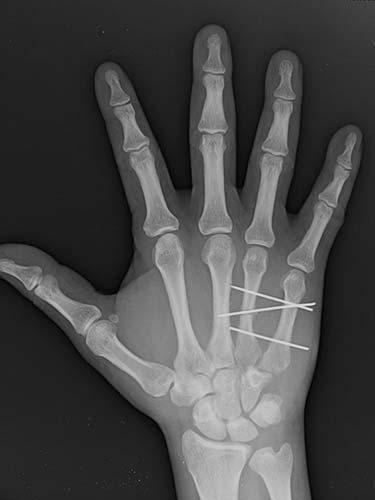

31 year old that suffered a broken bone in his hand while at work. Attempts were not possible at treating the patient without surgery because of the need to use his hand to help out with family obligations. He chose to have the hand treated with temporary wires that allowed him to help out with family obligations. The patient healed without any problems having regained full use of his hand.

- After